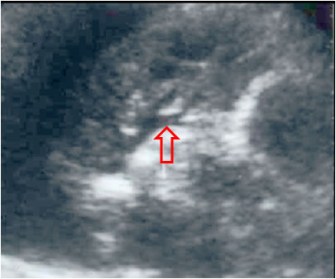

SIGNO DEL BRONCOGRAMA LÍQUIDO

Signo de atelectasia obstructiva en ecografía y TC. Corresponde a la presencia de bronquios distendidos, rellenos de líquido, en pacientes con obstrucción endobronquial. En ecografía estos bronquios se ven como estructuras lineales, ramificadas, con contenido hipoecoico (flecha). Además, falta el broncograma aéreo, que debería estar presente en la atelectasia del pulmón no obstructiva.